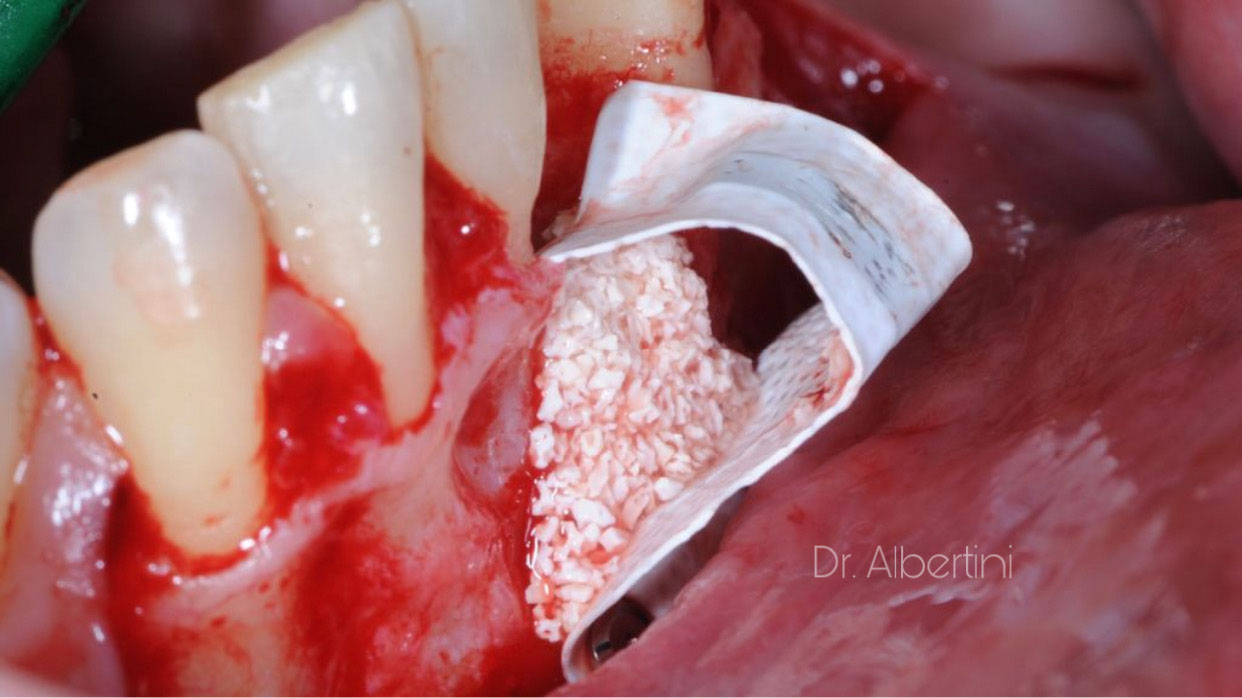

Dr. Mateo

Albertini